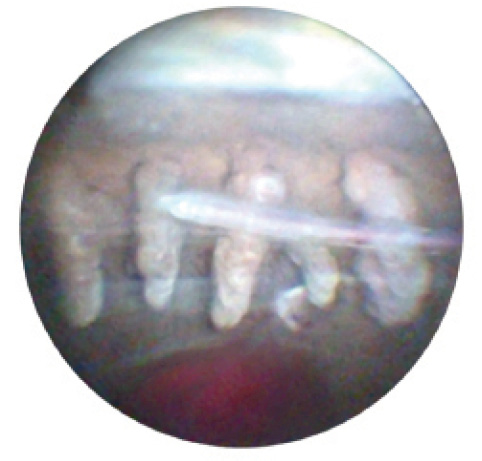

The 23-gauge endoscope is also useful for treating uveitis-glaucoma-hyphema (UGH) syndrome, which is most commonly caused by malposition of an IOL, with resultant contact with delicate uveal tissue. The causative pathology is often located just posterior to the iris. Direct visualization of this region can be helpful in diagnosis and treatment of the condition (Figures 1 and 2).

Figure 2. Haptic has extruded through the capsular bag, piercing the ciliary body.

Patient management in UGH can prove difficult, as the syndrome is characterized by chronic episodes of hyphema, ocular inflammation, and elevated intraocular pressure. Traditionally, anterior segment ultrasound biomicroscopy has been performed for visualization of the IOL, iris, and sulcus. If this technology is not available or is inconclusive, surgical intervention for hyphema or vitreous hemorrhage using endoscopy can greatly improve outcomes. In some cases, direct visualization of the haptic can allow repositioning of the IOL without explantation. Similarly, the 23-gauge endoscope may improve outcomes in vitrectomy for retained lens fragments, allowing a more thorough anterior vitrectomy and removal of lodged lens fragments in this region.